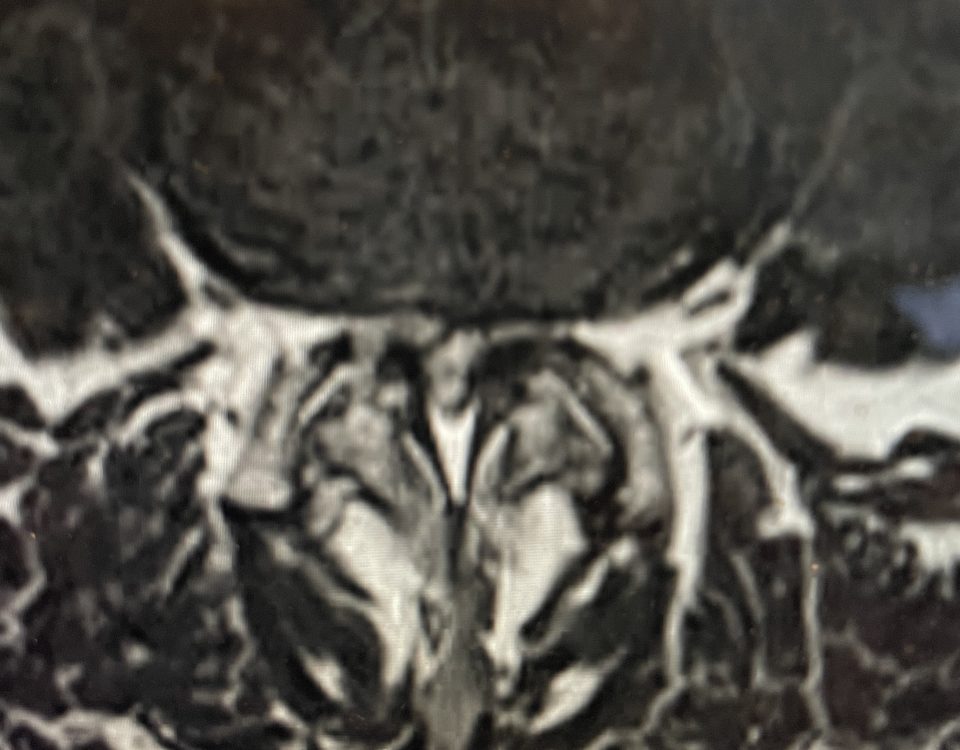

The spinal synovial cyst is one of the most interesting expressions of spinal instability. They emanate from the synovial lining of a degenerated facet joint that […]